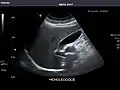

Kidneys: Right and left kidneys measure 11.5 cm and 12 cm in length respectively. No hydronephrosis. Small left lower pole kidney cyst.

Right kidney